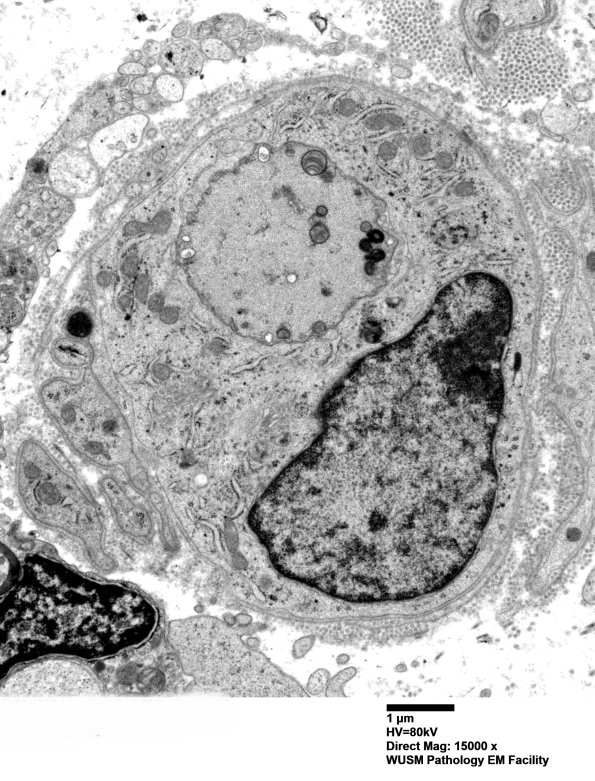

Washington University Experience | PERIPHERAL NEUROPATHY | 12 ANTI-MAG NEUROPATHY | 4D4 (Case 4) Nerve_014 - Copy

4D4,5 Scattered demyelinated axons were encountered. (electron micrographs)